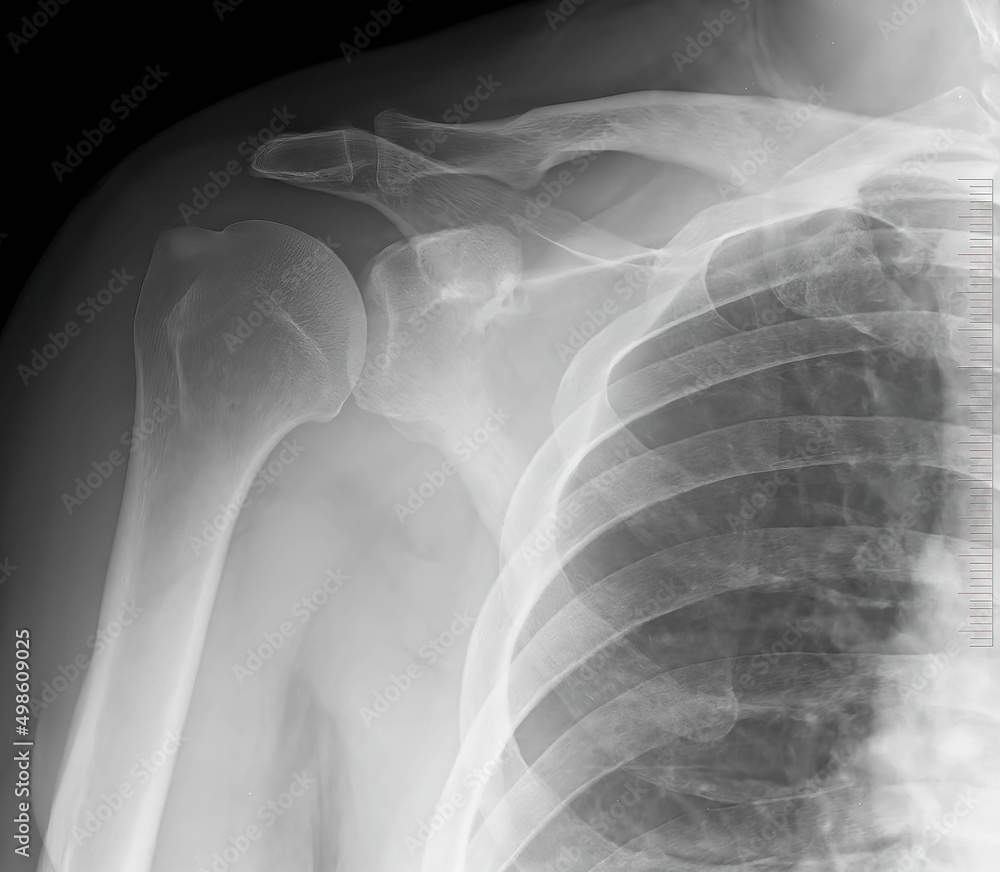

X Ray For Shoulder Joint . Clinicians typically use the axillary view in evaluating subluxations and dislocations of the humeral head, generally centered on the glenoid and round in contour. This view helps in visualizing potential fractures or dislocations to the proximal humerus and shoulder girdle in a trauma setting. Articular surface of the humeral head covered hemispherically with hyaline cartilage. This projection is also useful in evaluating. Additionally, this view is useful in assessing for. Mri is best for evaluating soft tissue structures and evaluating bone contusions or trabelcular microfractures. The shoulder series is fundamentally composed of two orthogonal views of the glenohumeral joint including the entire scapula. Ideally, a shoulder radiograph series will provide adequate views of the clavicle, acromioclavicular joint (acj), glenohumeral joint.